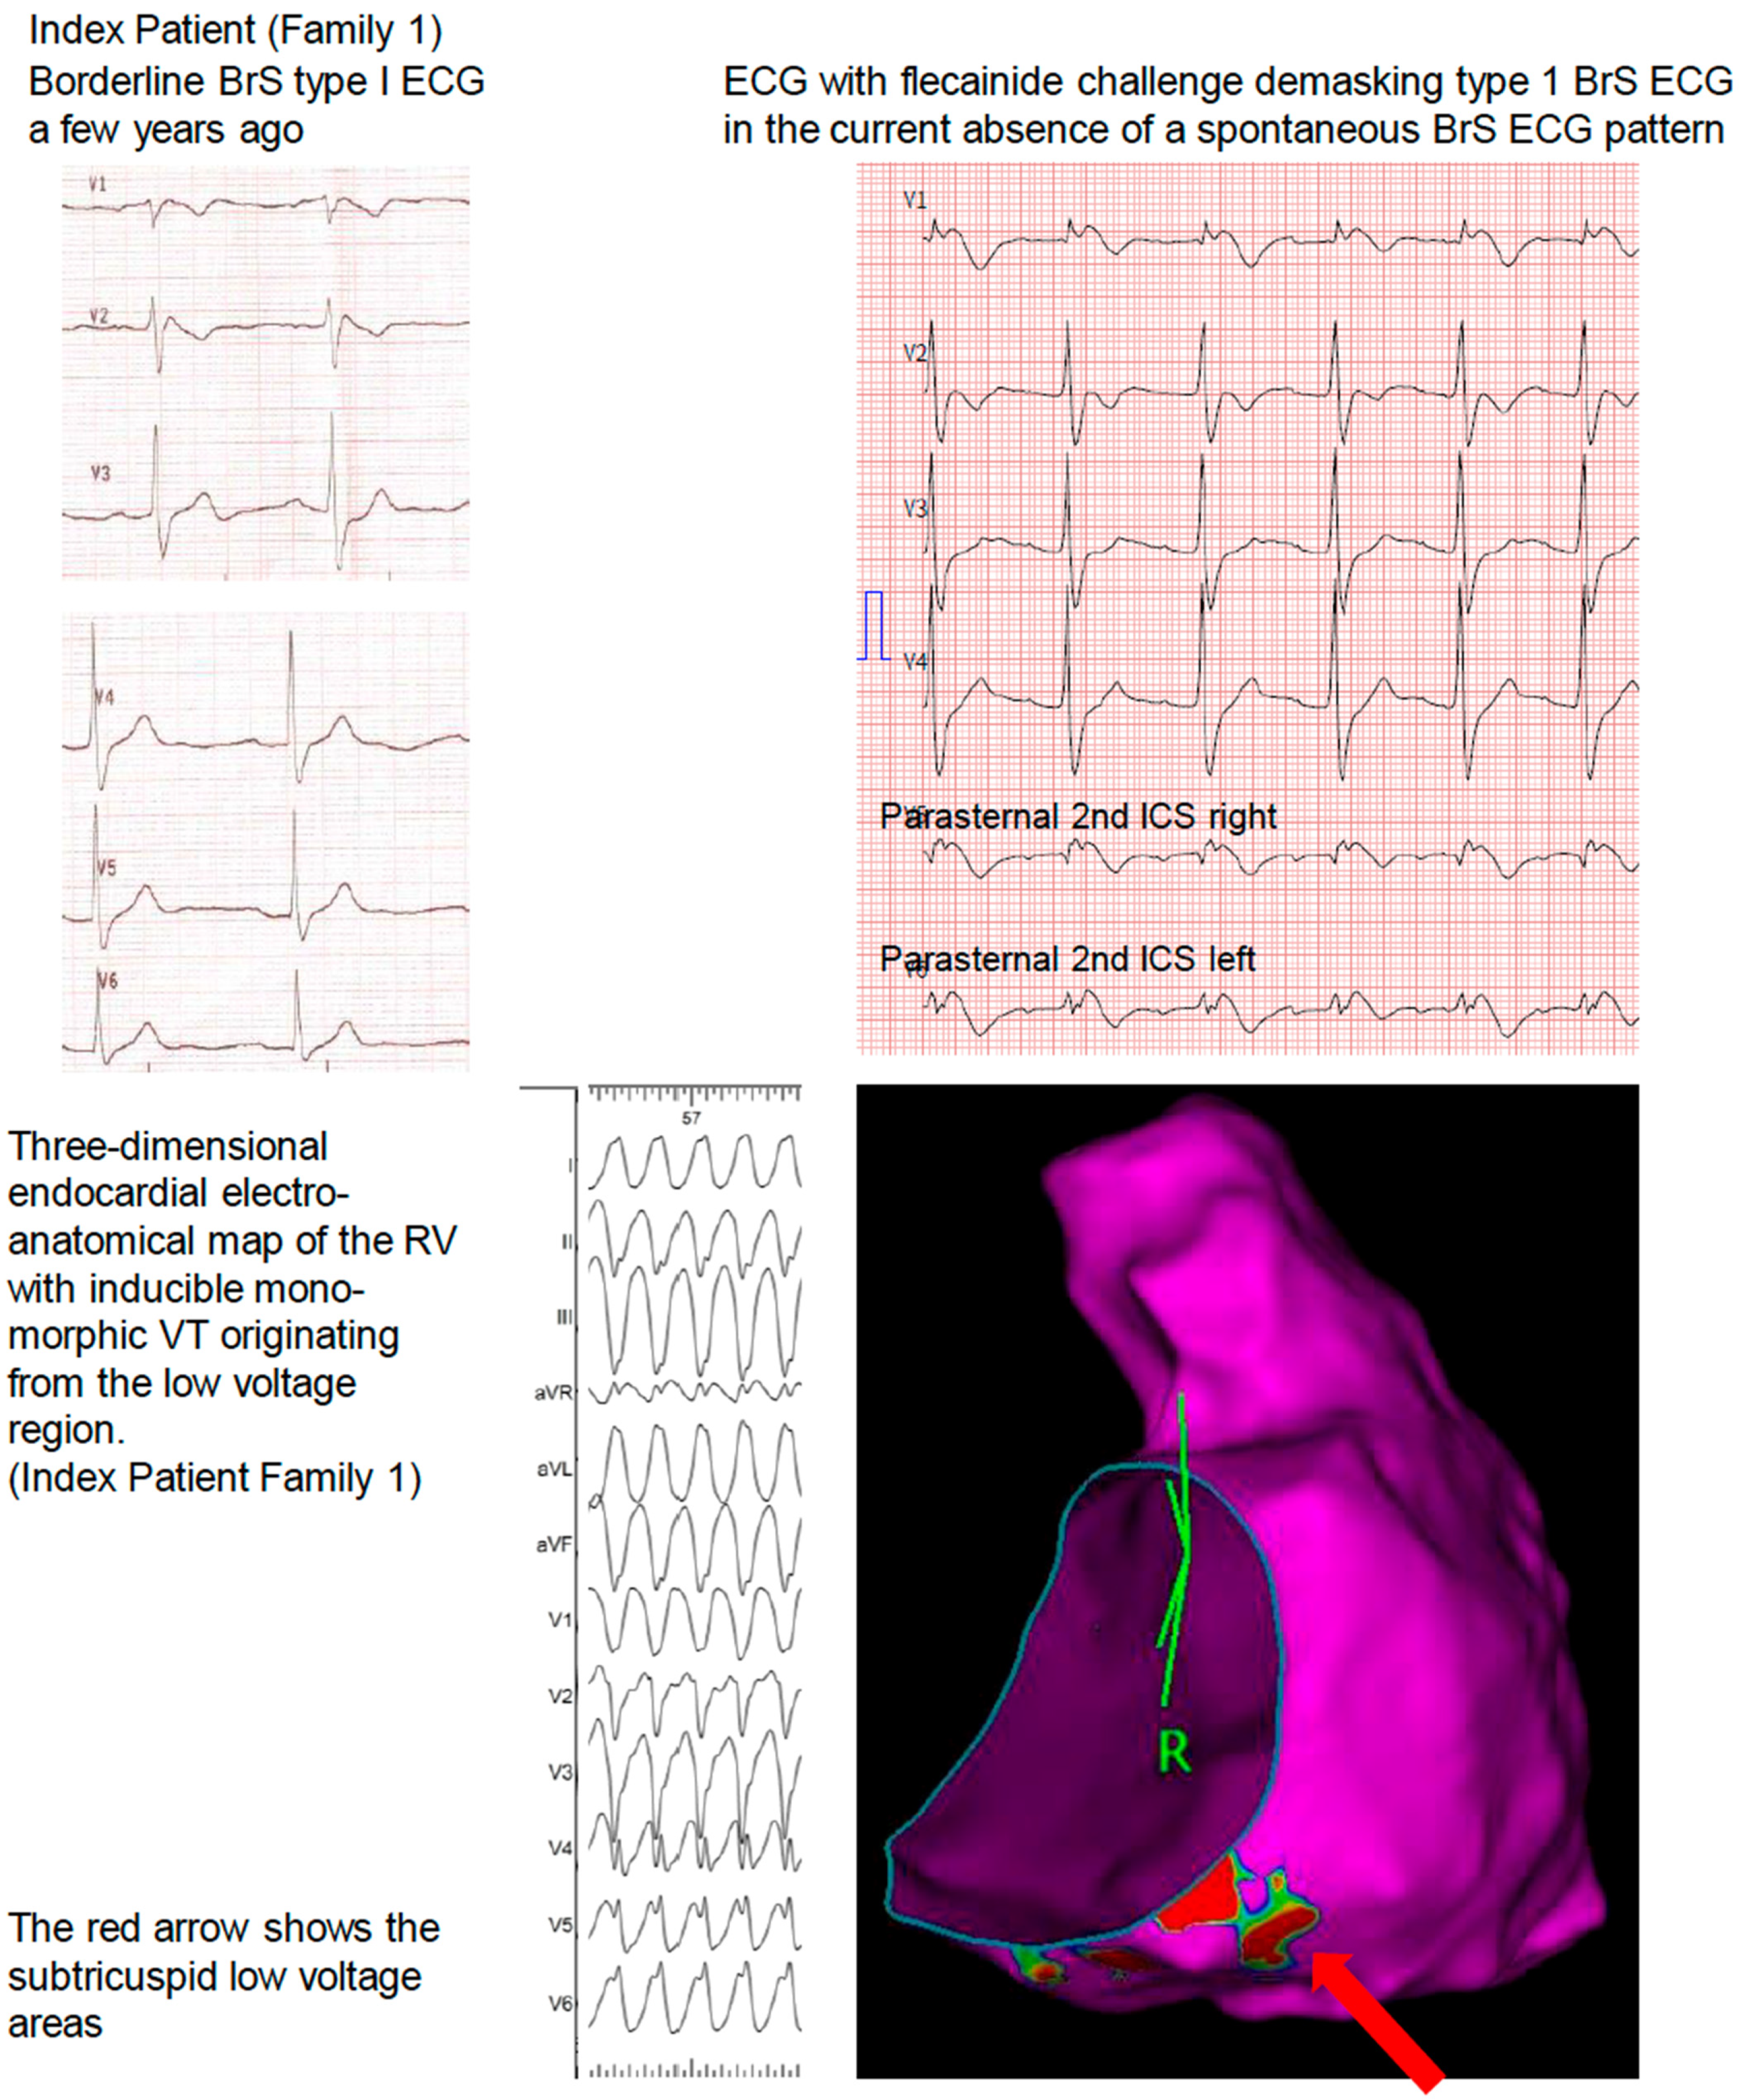

3.1. Family 1